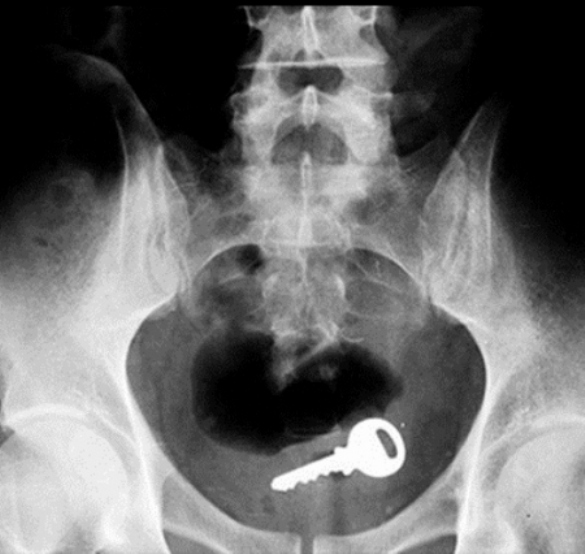

Key